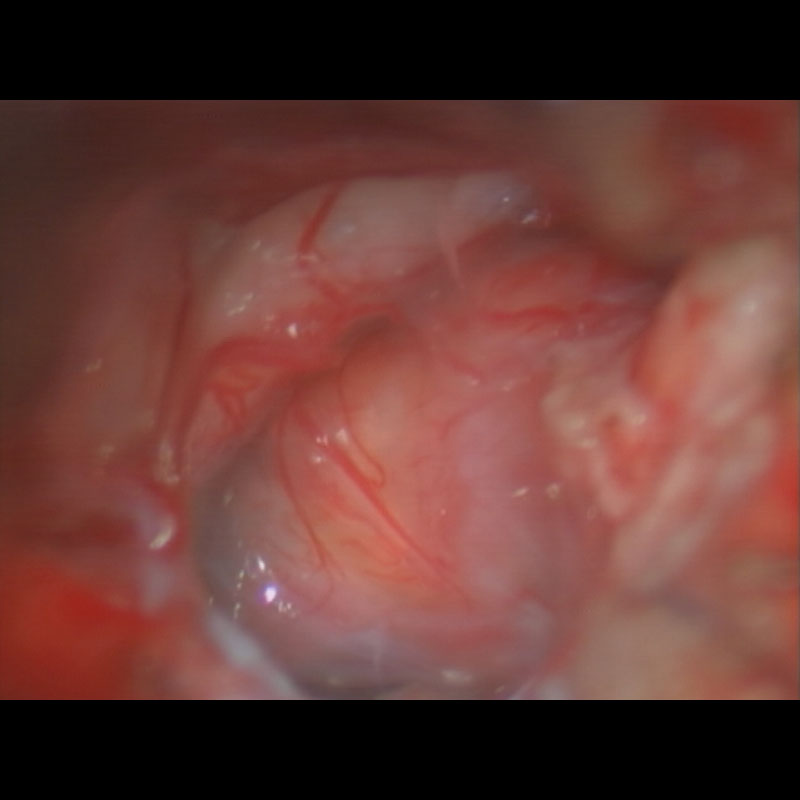

360

'22年12月

70代

右前頭葉膠芽腫

頭蓋内腫瘍摘出術

No.’22_117 摘出 前

No.’22_117  摘出 中

No.’22_117 摘出 後